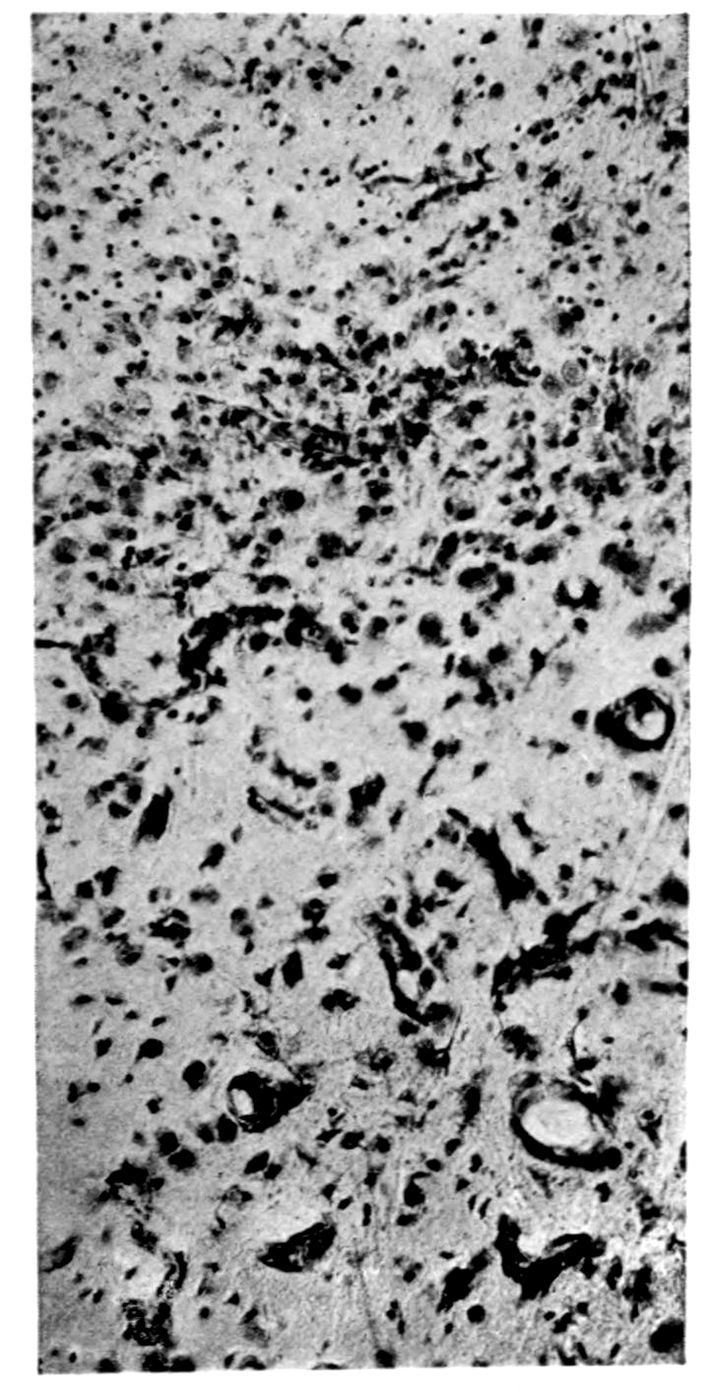

Microscopic findings are here presented merely in sufficient detail to establish the diagnosis. The left superior frontal gyrus shows extensive and somewhat irregular cellular and fibrillar gliosis of the plexiform layer, together with an increase of thickened vessels having lymphocytes and plasma cells in their sheaths.

The perivascular infiltrations are most extensive in the lower layers of the cortex. The lamination is in places thoroughly obscured, except that representatives of the layer of large external pyramids are almost always demonstrable.

The layer of medium-sized pyramids has undergone more numerical loss of elements than have the other layers.

Gliosis of white matter.

Specimens from the cerebellum show a destructive process of great severity, but a little irregular in extent, affecting chiefly the Purkinje cell belt. The Purkinje cells are often absent throughout one side of a given lamina, and there has ensued a dense accumulation of neuroglia cells along a former Purkinje cell belt, together with a considerable gliosis of the molecular layer. Considerable gliosis of the white matter, both diffuse and perivascular in distribution.

Perivascular plasma cell infiltrations as in cerebrum, but largely meningeal or in the white matter.

Sections from the corpora striata demonstrate a mild and early granular ependymitis, considerable subependymal gliosis of cellular type, considerable perivascular gliosis in the white portions of the tissue, and a moderate infiltration of perivascular sheaths with pigmented cells, lymphocytes, and plasma cells. There is little evidence of alteration in the nerve cells. Some are unevenly pigmented.

Rod cells (Stäbchenzellen) in paretic neurosyphilis. Photographed by Dr. A. M. Barrett.

Granular ependymitis—microscopic appearance of a marked example of “sanding” of ventricle.

41Characteristic and constant in paretic neurosyphilis is the Plasmocytosis and Lymphocytosis, Perivascular in distribution about small cortical vessels. There is also a characteristic (though characteristically less prominent) Plasmocytosis and Lymphocytosis, Meningeal in distribution. The pleocytosis of the spinal fluid, almost constant though variable in amount in life, is an indicator of the meningeal picture and less directly of the parenchymatous picture.

Granular Ependymitis (“sanding” of ventricle floors) is characteristic and may be regarded as part of the parenchymatous picture. This ependymitis is an indicator how chemical changes could be readily produced at least in the ventricular fluids, since the limiting membranes of the nerve tissue are here subject to multiple breaks. The “sanding” is a neuroglia reaction to these multiple small breaks (Weigert’s explanation).